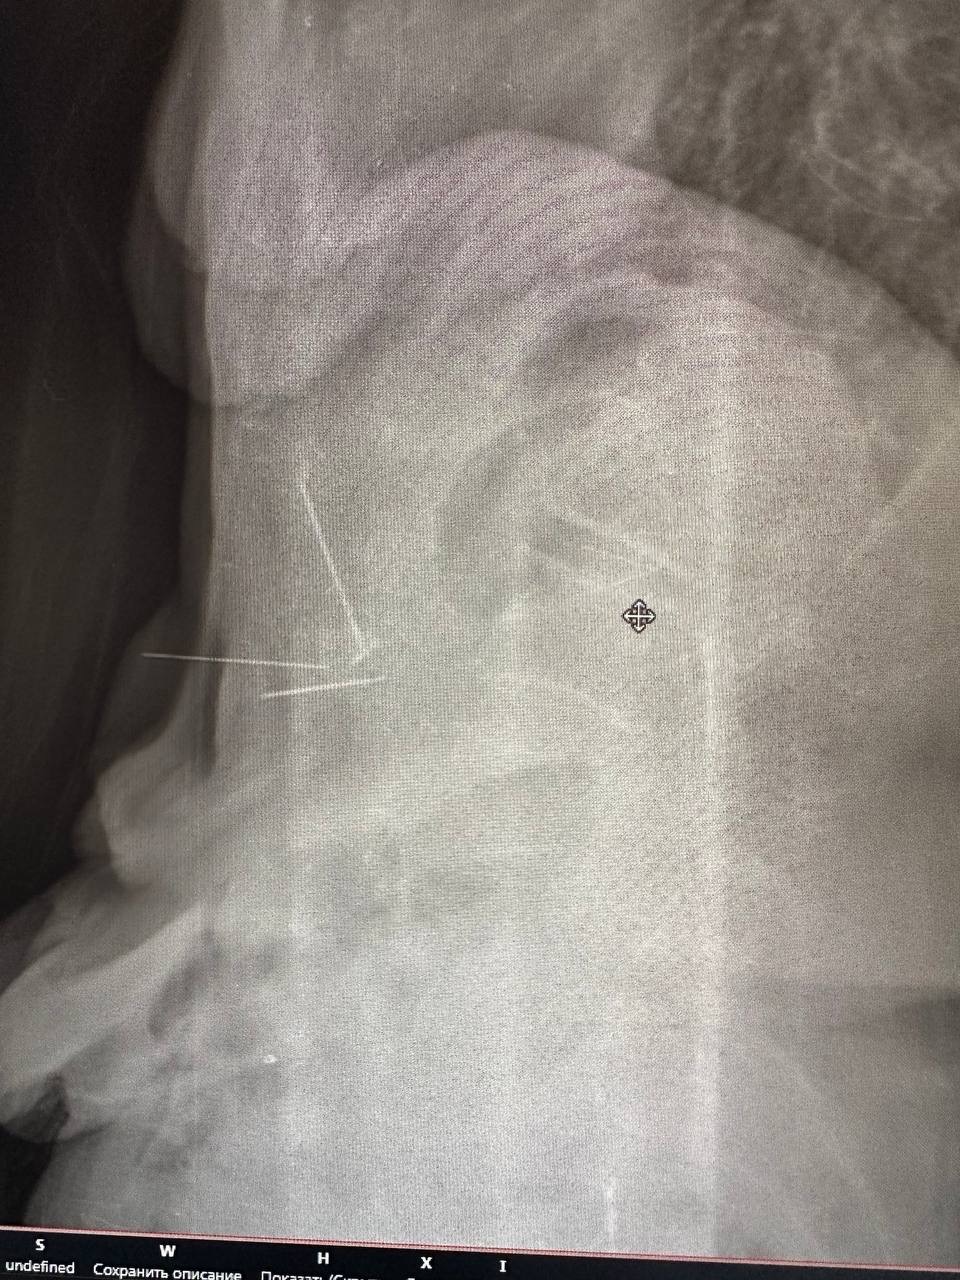

Вот случай, который был у нас в отделении. Поступила пожилая женщина с тремя иглами в животе, которые находились там так давно, что были уже с признаками коррозии.